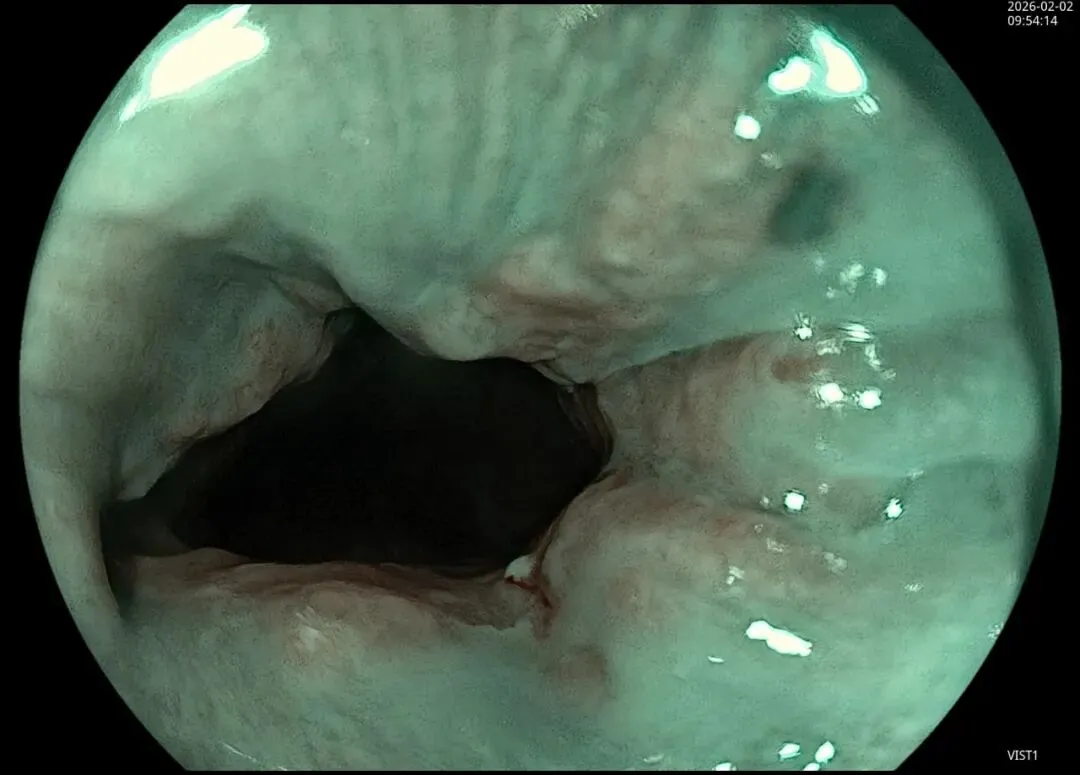

这一期不用码字,挺好的,很可惜一直没机会听过胡导讲的关于这个“花环征”的大课,学习内容来源于雨夜大师的号花环征:AIG背景的胃食管结合部的黄色颗粒状隆起及半透明“泡状”改变

补充自己在两例A型胃炎/AIG 观察到的“花环征”,巩固下学习效果。。。

case2:(made in china机子)👇

1.白光表现为胃食管交界处黄色颗粒状隆起及半透明“泡状”改变

2.窄带光下可见颗粒状隆起呈褐色改变,放大可见细微网状血管结构及半透明“泡状”改变

3.典型病理是鳞状上皮局灶性变薄及黏膜固有层显著增生、扩张的贲门腺。